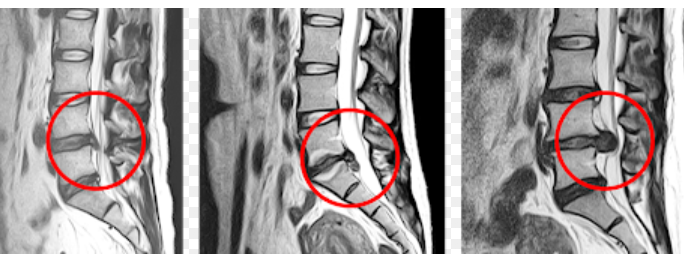

📌 허리디스크란?

허리뼈(요추) 사이에는 디스크(추간판)라는 젤리 같은 구조물이 있어 충격을 흡수합니다.

그런데 나이가 들거나 무리한 동작으로 이 디스크가 밀려나와 신경을 눌러 통증을 유발하는 것이 허리디스크입니다.

📌 허리 협착증이란?

협착증은 척추관이 좁아져서 신경이 눌리는 질환입니다. 나이가 들수록 척추 주변 뼈와 인대가 두꺼워지고, 디스크도 조금씩 튀어나오면서

신경이 눌리는 공간이 점점 줄어들게 됩니다.

즉, 디스크보다 더 나이와 관련된 퇴행성 질환으로 보는 것이 맞습니다.